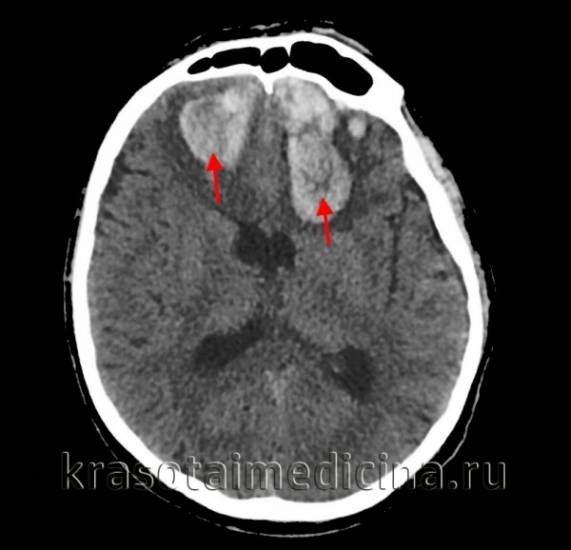

• КТ головного мозга. На томограммах внутримозговая гематома выглядит как очаг гомогенной плотности округлой или овальной формы. Если гематома возникла из-за ушиба головного мозга, она обычно имеет неровные контуры. Со временем плотность гематомы уменьшается до изоплотного состояния, соответствующего плотности мозговой ткани. Для малых гематом этот процесс занимает 2-3 недели, для средних — до 5 недель.

Церебральные гематомы бывают единичными и множественными, односторонними и двусторонними, острыми, подострыми и хроническими. Хроническая форма развивается через 21 день после геморрагии. Основными триггерами являются артериальная гипертония и атеросклероз (70-80% случаев), а также аневризмы, сосудистые мальформации и механические повреждения при черепно-мозговых травмах.

В диагностике нейровизуализация играет важную роль. Первоначально для исследования головного мозга назначают компьютерную томографию (КТ). Этот доступный метод позволяет быстро определить наличие крови в веществе головного мозга, а также расположение и объем сгустка. Информативность КТ максимальна через 2-3 недели после появления гематомы (максимум 5 недель). В этот период участок внутримозговой гематомы (ВМГ) имеет повышенную плотность, что облегчает диагностику, и можно ограничиться одной КТ.